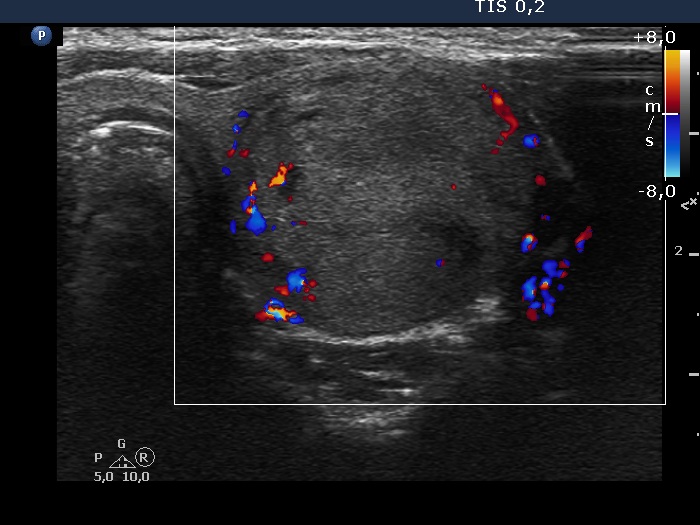

Left lobe, transverse scan, color Doppler mode. The lesion has perinodular blood flow.